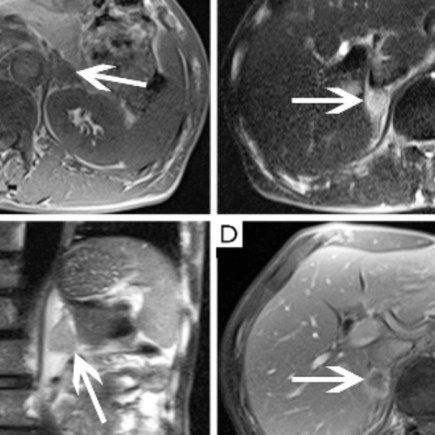

Компьютерная томография (КТ) надпочечников

Компьютерная томография (КТ) надпочечников — это высокотехнологичный метод визуализации, который позволяет получить детальные изображения этих органов. Надпочечники — это маленькие железы, расположенные над почками, которые играют ключевую роль в эндокринной системе, вырабатывая гормоны, такие как адреналин, кортизол и альдостерон. КТ надпочечников используется для диагностики различных заболеваний, включая опухоли, кисты и адреналиновую недостаточность. Показания для проведения …